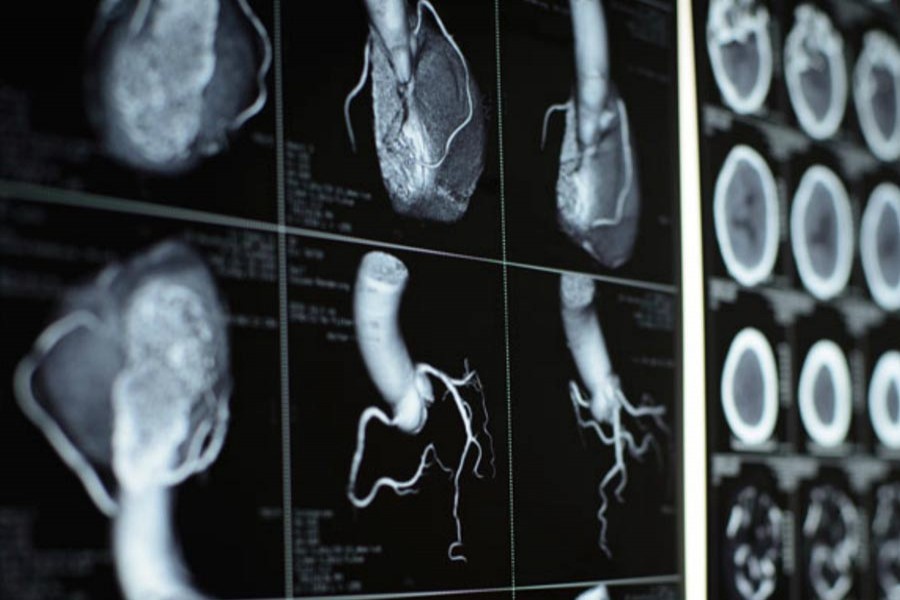

A new method of analysing images from CT scans can predict which patients are at risk of a heart attack years before it occurs, researchers say.

The technology, developed by teams at Oxford University and institutions in Germany and the United States, uses algorithms to examine the fat surrounding coronary arteries as it shows up on computed tomography (CT) heart scans.

“With the new technology that we have we can achieve this by analysing simple CT scans.”

Currently, CT scans tell a doctor when an artery has already become narrowed by plaque.

With the new technology, for which the researchers hope to gain regulatory approval on both sides of the Atlantic within a year, doctors will be able to say which arteries are at risk of narrowing.